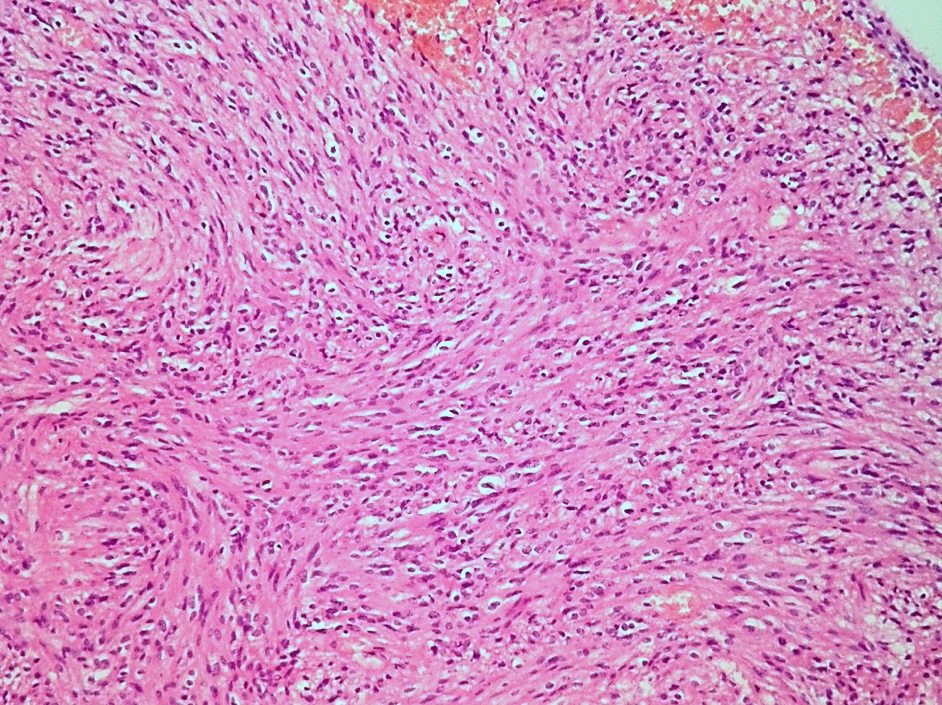

Microscopic (histologic) description

- Cellular tumor with typically sharply circumscribed borders; may be infiltrative

- Monomorphic round to oval cells with speckled chromatin

- Perivascular pseudorosettes, true ependymal rosettes, lumina and fibrillar areas

- Morphologic subtypes have no clinicopathological significance and include papillary, clear cell and tanycytic

Microscopic (histologic) images

Cytology description

- Spindle shaped cells with oval to elongated nuclei and delicate fibrillary cytoplasm with occasional intracytoplasmic lumina, which can be arranged around blood vessels

- Occasional nuclear grooves and inclusions can be seen (J Pathol Transl Med 2019;53:104)